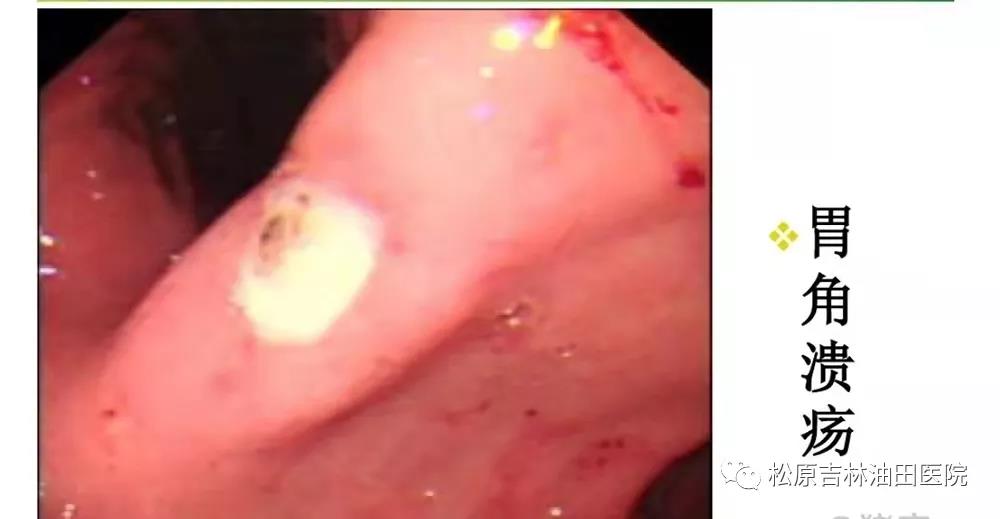

(2)消化道溃疡一由于幽门螺杆菌寄生在胃部破坏了胃黏膜的天然保护屏障和修复功能,致使胃黏膜、十二指肠黏膜、食道黏膜很容易受到胃酸、胆汁等物质的腐蚀却不能够有效修复,从而引发消化性溃疡。

(3)胃癌及胃黏膜相关性淋巴样组织样恶性淋巴瘤